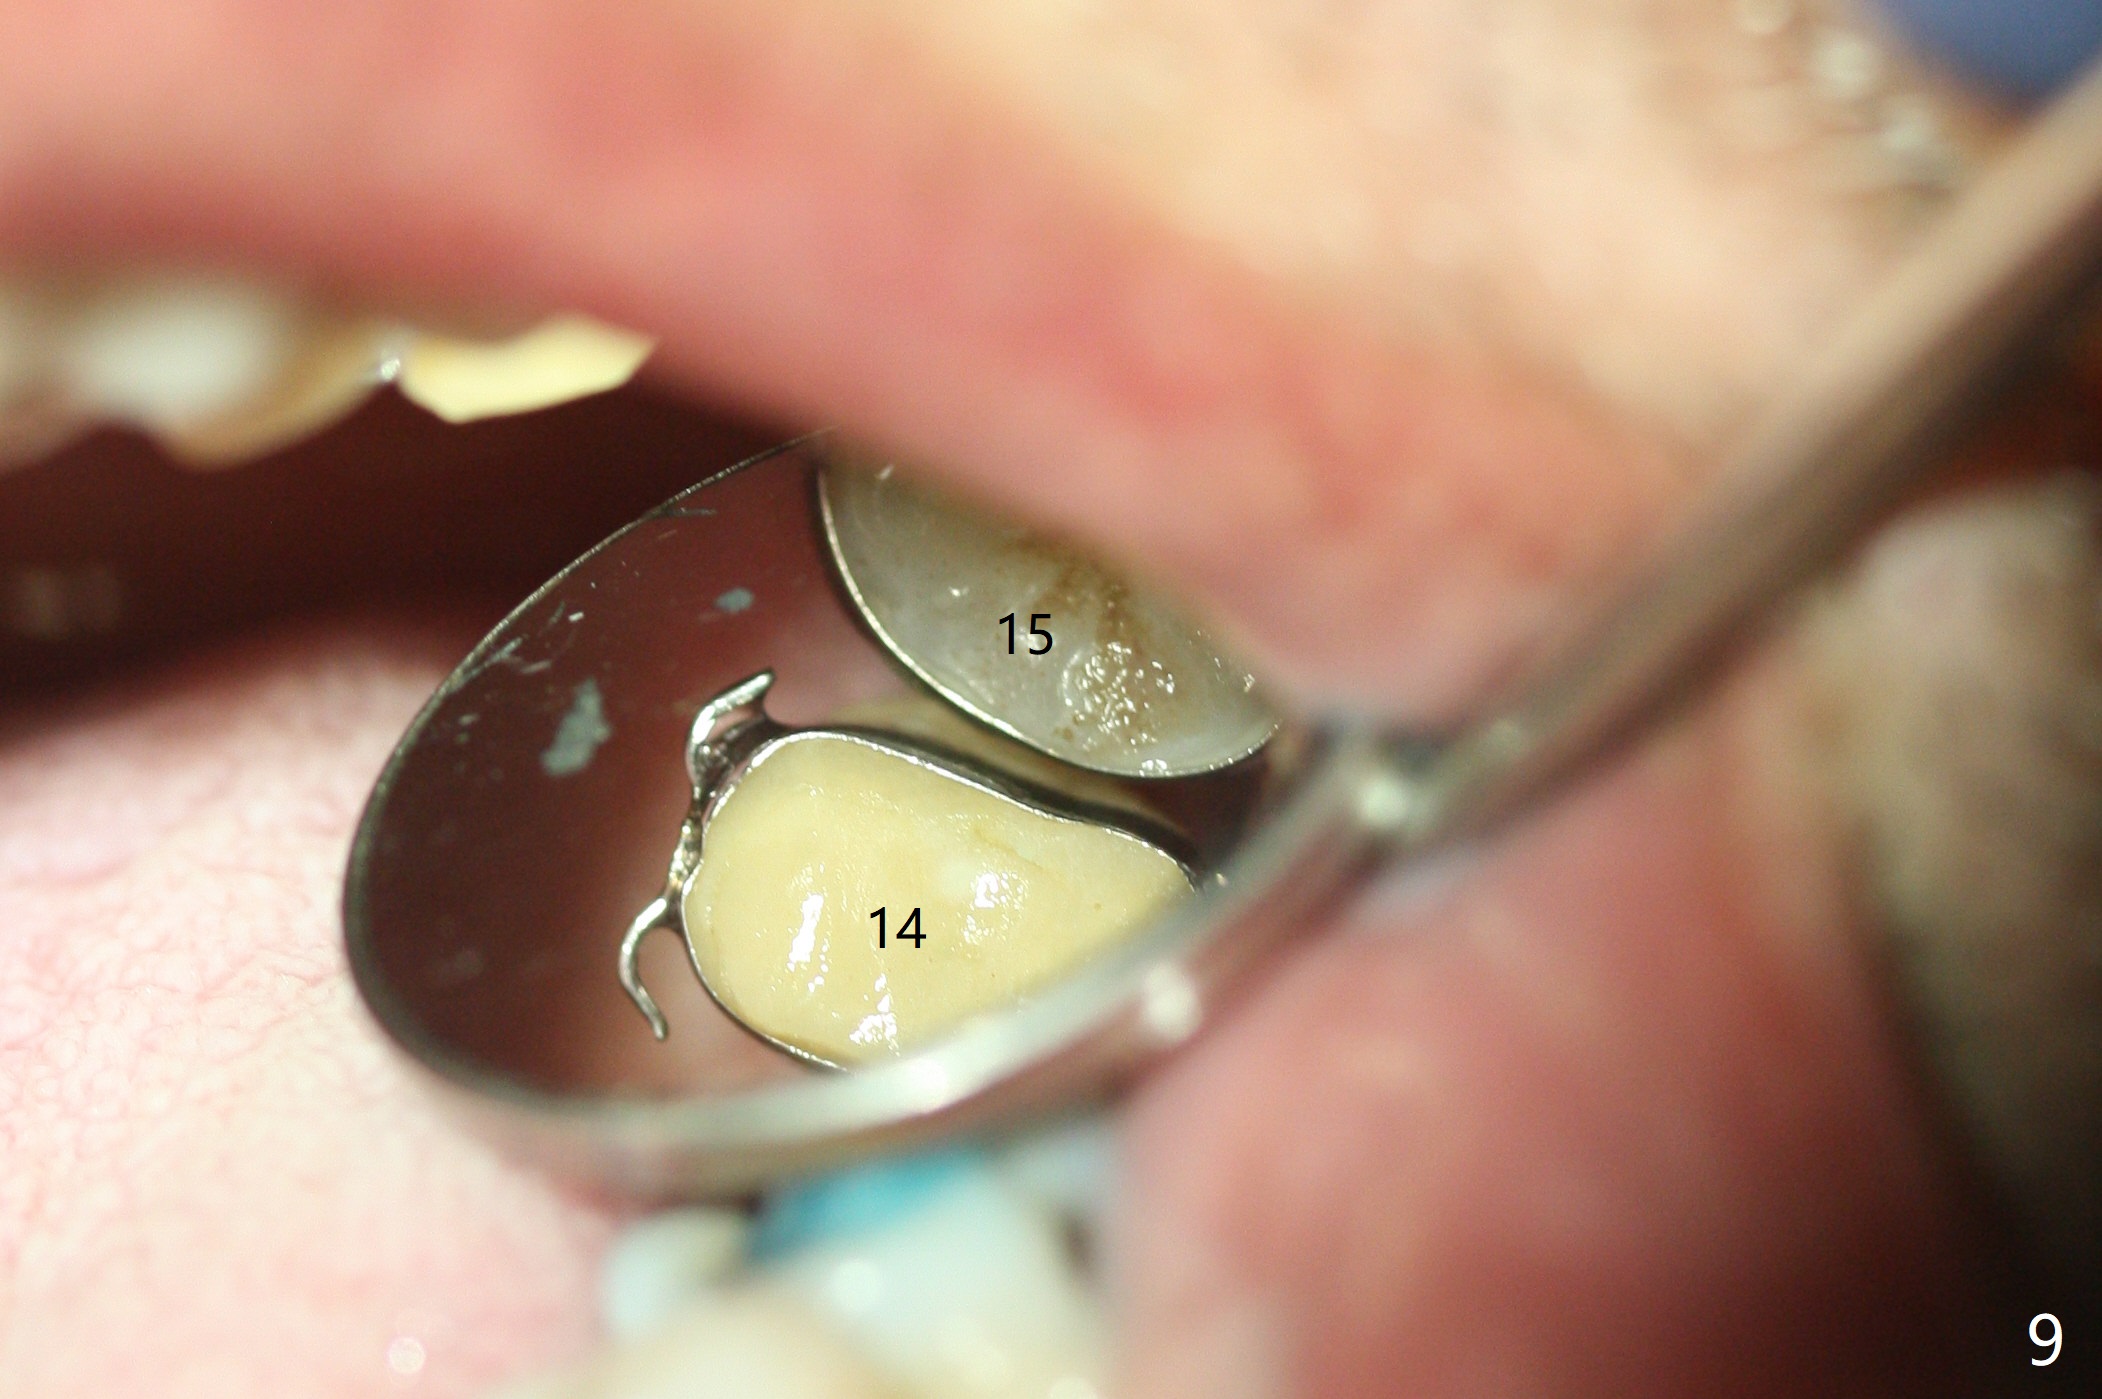

Six months post 2nd placement at #14, the 5x11 mm IBS implant is unstable. The patient smokes a cigarette a day.  After implant removal, the palatal wall of the osteotomy is intact, although low.  With removal of minimal granulation tissue, a 5x10 mm IS dummy implant is placed with stability and slightly subgingival palatal (Fig.1,2).  A 5x8.5 mm definitive implant is placed with ~ 40 Ncm and 3-4 mm subgingival palatal (Fig.3,4).  A 5.7x5.5(5) mm abutment is placed to hold periodontal dressing in place.  If the implant fails again, bone graft should be placed.  The abutment and implant are stable 4.5 months postop (Fig.5); a provisional is fabricated for progressive loading.  The provisional at #14 is narrow mesiodistally, while the tooth #15 is mesially tilted and shifted because of chronic periodontitis and 1 year 4 months of edentulism (Fig.6*).  Limited orthodontics is necessary prior to final restoration.  The 1st step is to raise the occlusion with #14 temporary reline (Fig.7 *); the tooth #15 is distalized initially with a separator, which is inefficient.  It appears that brackets and bands should be placed for distalization.  A month post banding, open coil spring is placed between #14 and 15; with occlusal composite on the opposing tooth (#19) (Fig.8), the tooth #15 is distalized instantly probably related to its periodontal condition (Fig.9 mirror view).  The tooth #15 is further distalized 2 weeks post open coil spring placement (Fig.10).  To act an anchorage, the abutment needs to be torqued with wrench (25-30 Ncm) and the provisional has to be permanently cemented.  The distalization appears to be ~ 1 mm shy 1.5 months post open coil (Fig.11).